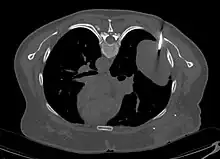

Les tumeurs fibreuses solitaires pleurales sont visualisées sur la radiographie thoracique comme des masses bien délimitées. Les clichés radiologiques standards sont cependant peu utiles pour les autres localisations[17].

En tomodensitométrie[20],[31], quelle que soit la localisation, une tumeur fibreuse solitaire apparaît comme une masse tissulaire ovoïde ou lobulée, bien délimitée, refoulant les structures voisines sans les envahir. Elle se rehausse fortement après injection de produit de contraste. Les tumeurs de petite taille sont homogènes, mais les plus volumineuses présentent des plages hétérogènes de nécrose et d'hémorragie intra-tumorale. Il n'y a pas habituellement de calcifications et, lorsqu'elles sont présentes, elles sont de petite taille[31]. Les tumeurs malignes peuvent se présenter accompagnées de nodules pulmonaires métastatiques, et tendent à être plus volumineuses et plus hétérogènes[42].